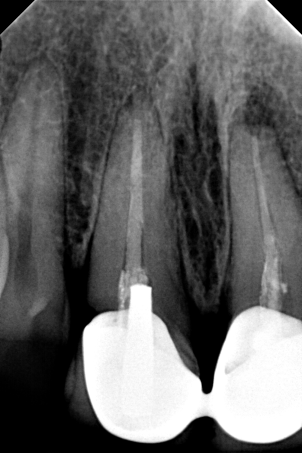

Περιστατικό – Επανάληψη απονεύρωσης και προσθετικής

Η ασθενής παρουσιάστηκε στο ιατρείο με την επιθυμία να ξανακολληθούν οι στεφάνες της στους δυο κάτω αριστερούς προγομφίους, γιατί τον τελευταίο καιρό της αισθανόταν “λίγο χαλαρές”.

Η κλινική εξέταση των δοντιών έδειξε κάτι πιο πολύπλοκο απ΄ αυτό που περιέγραφε η ασθενής. Οι στεφάνες ήταν πράγματι χαλαρές και δεν προσάρμοζαν πάνω στα δόντια, γιατί τα δόντια κάτω από τις στεφάνες είχαν επανατερηδονιστεί.

Η ακτινογραφική εξέταση αποκάλυψε ότι και τα δύο δόντια είχαν απονευρωθεί στο παρελθόν, έφεραν το καθένα στο εσωτερικό χυτό μεταλλικό άξονα και στο ακρορρίζιο διαπιστώθηκε μια περιακρορριζική αλλοίωση. Η αλλοίωση αυτή μαρτυρά τη φλεγμονή του δοντιού στο άκρο της ρίζας.

Μετά από συνεννόηση με την ασθενή αποφασίστηκε το παρακάτω σχέδιο θεραπείας:

1. Αφαίρεση των παλιών στεφανών (θηκών δοντιού)

2. Αφαίρεση του χυτού μεταλλικού άξονα από το εσωτερικό του ριζικού σωλήνα

3. Επανάληψη της απονεύρωσης

Αφού ολοκληρώθηκαν οι παραπάνω εργασίες πραγματοποιήθηκε αποκατάσταση των δοντιών με άξονες υαλονημάτων και κατασκεύη καινούριων στεφανών. Οπώς φαίνεται και στην τελική ακτινογραφία 6 μήνες μετά την διεκπεραίωση του σχεδίου θεραπείας η φλεγμονή στο ακρορρίζιο του δοντιού είχε ήδη υποχωρήσει.

ΠΡΙΝ

Έλεγχος αφαίρεσης άξονα και παλιάς απονεύρωσης

Τελική ακτινογραφία